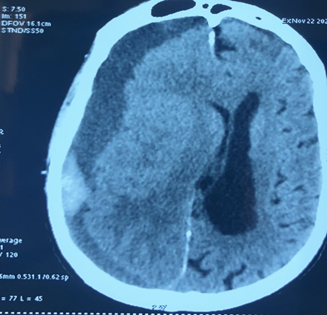

The argument can be made that every boxer is a high-risk fighter. Boxing as a sport can never be made totally safe. Close medical supervision of the sport, robust medical protocols designed to protect fighters help to make the sport safer. In spite of our best efforts, boxers will unfortunately continue to succumb to injuries either in the ring itself or in the immediate aftermath of a bout. Traumatic subdural hematoma (SDH) remains the most common cause of boxing related mortality.